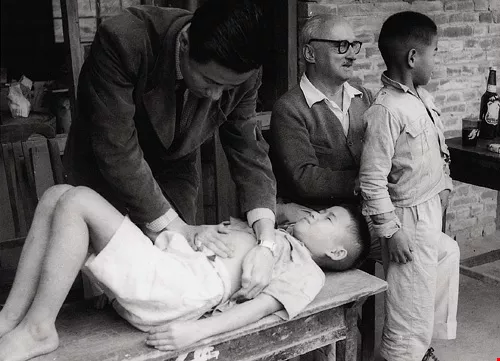

台灣光復初期,衛生及醫療條件不佳,傳染病頻仍,國外醫療及慈善團體經常派員來台協助。如今面對新興傳染病,人們在恐懼之餘,如何兼顧人權,已成為新議題。